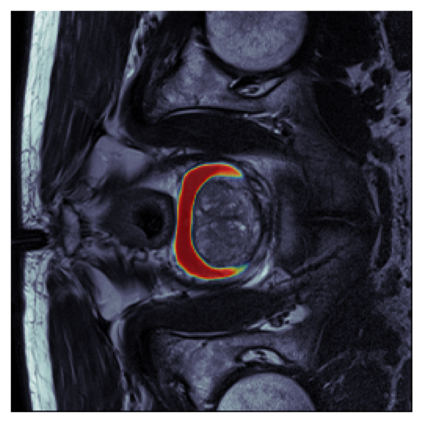

The sigmoid activation is the standard output activation function in binary classification and segmentation with neural networks. Still, there exist a variety of other potential output activation functions, which may lead to improved results in medical image segmentation. In this work, we consider how the asymptotic behavior of different output activation and loss functions affects the prediction probabilities and the corresponding segmentation errors. For cross entropy, we show that a faster rate of change of the activation function correlates with better predictions, while a slower rate of change can improve the calibration of probabilities. For dice loss, we found that the arctangent activation function is superior to the sigmoid function. Furthermore, we provide a test space for arbitrary output activation functions in the area of medical image segmentation. We tested seven activation functions in combination with three loss functions on four different medical image segmentation tasks to provide a classification of which function is best suited in this application scenario.